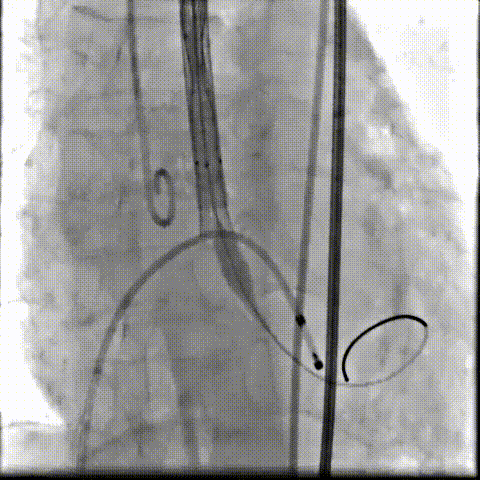

根部造影可见返流,23mm球囊预扩张

无窦侧严重钙化及融合影响,

瓣膜(AV29)释放不稳出现反复上跳,2次回收尝试

重新定位释放,

钙化及融合挤压导致瓣膜(AV29)下滑位置偏深

第三次回收重新定位

工作位造影位置良好,完全脱钩释放瓣膜(AV29)

考虑支架腰部挤压,23mm球囊充分后扩后形态良好,

极微量瓣周漏